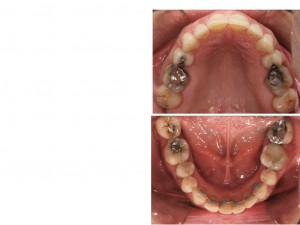

Motivo dell’intervento

Valutazione della recessione in zona incisiva inferiore.

Anamnesi

Discrepanza basale antero posteriore con divergenza aumentata (chirurgica), presenza di una esoinclinazione degli incisivi inferiori, compensatoria rispetto alla II classe basale

Trattamento

Arretramento della dentatura e trattamento compensatorio con ext 15-25-35 e chiusura spazio 37